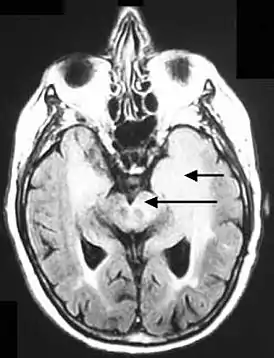

![]() Аксиальная FLUID МРТ, демонстрирующая инфильтративный рост опухоли с вовлечением обеих лобных долей (короткая стрелка) и чёрного вещества (длинная стрелка). | |